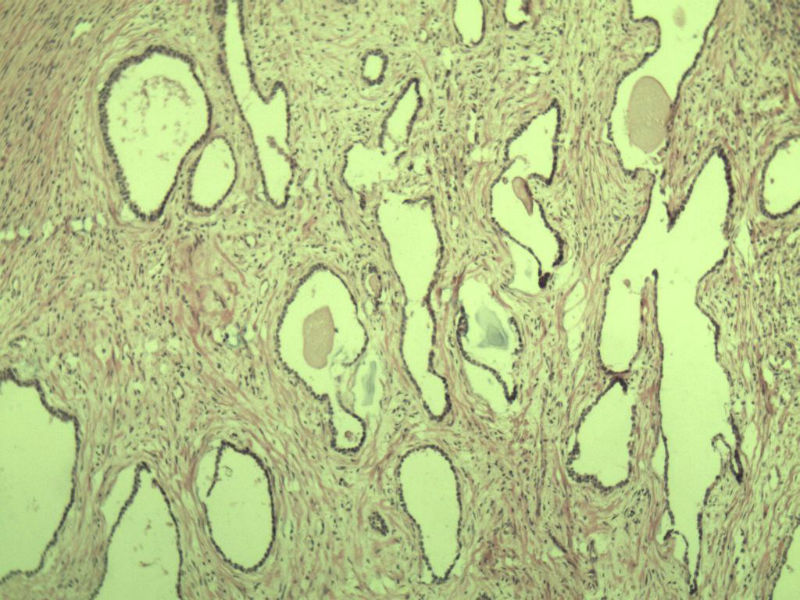

男 75岁 因排尿困难半年行前列腺切除术,体积 4 × 3 × 2.5 cm3,切面灰白,实性,质韧。请各位老师看看 有问题没? 谢谢了!

良性前列腺增生伴尿路上皮化生

前列腺增生症伴鳞化

前列腺增生伴尿路上皮鳞化及Brown巢形成,未见恶性。